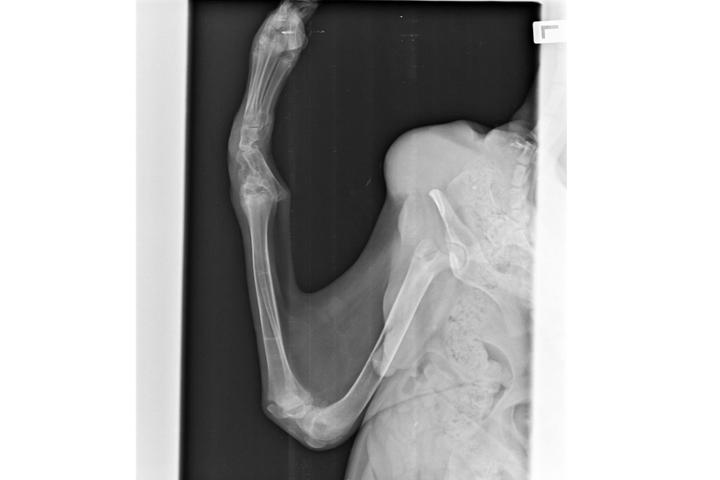

Maylo es un cachorro de unos 6 meses, al que iban a dormir porque no podía andar y no dudamos ni un momento en hacernos cargo de el. No tenemos un diagnostico claro de el, ya que no conocemos su pasado y qué es lo que le pasó, pero tiene una fractura en la parte baja de la columna que ha hecho que pierda toda la sensibilidad de sus patas traseras y se quede inmóvil. Vamos a necesitar mucho apoyo ya que los presupuestos de amputacion rondan los 600€/pata. ¿Nos ayudas? ➡️@mayloconruedas

Con este teaming queremos poder recaudar al menos los 600€ que costaría amputar 1/3 de la patita tiesa que tanto le molesta, y una vez eso, valorar si también quitar la que tiene doblada hacia atrás